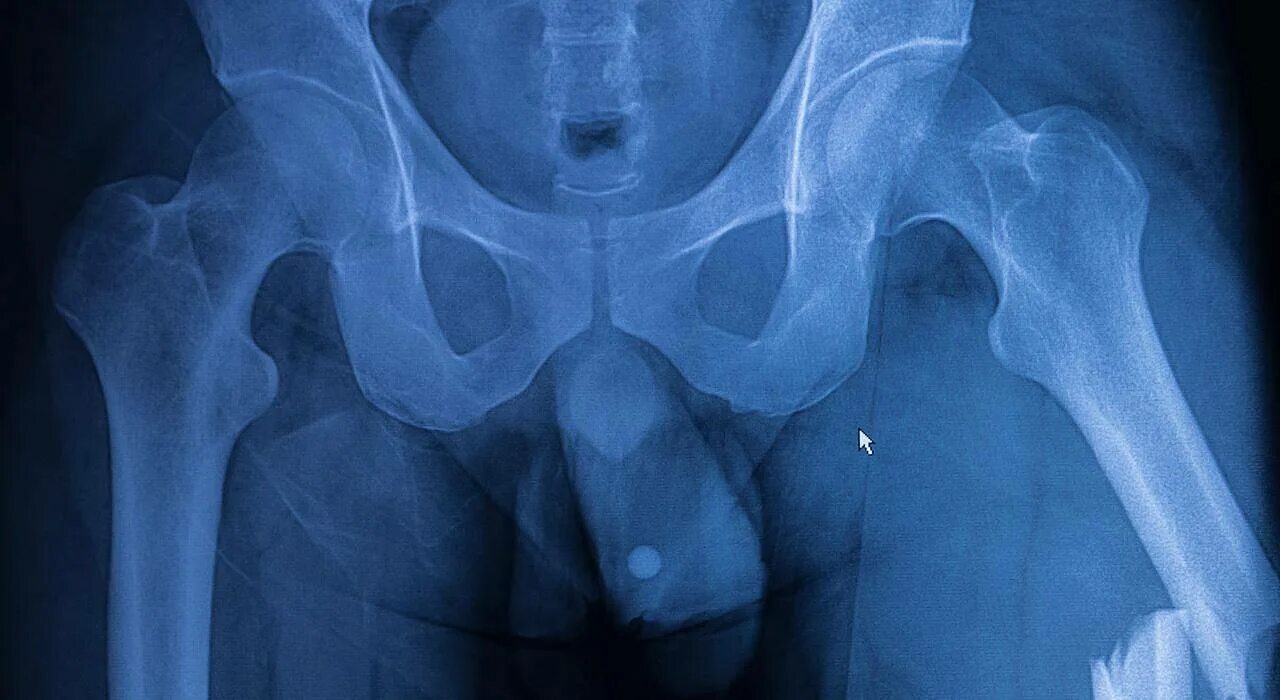

Проекции рентгена тазобедренного сустава